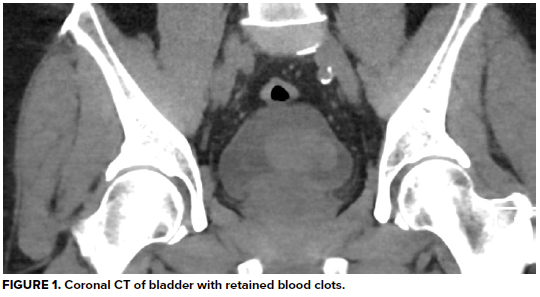

Urinalysis demonstrates 3+ blood and >50 RBC/hpf, but negative leukocyte esterase, negative nitrates, and no bacteria. His hemoglobin is at baseline, as are his BUN and creatinine, consistent with stage 3 CKD. A CT abdomen/pelvis without contrast reveals a large heterogeneous right renal mass with surrounding perinephric stranding, concerning for primary renal malignancy. There is also hyperdense material in a moderately distended bladder most likely reflecting blood clots, as well as scattered periaortic adenopathy which, given the context, raises concern for locally metastatic disease. He is unable to void spontaneously again, even after a fluid bolus.

Hemorrhagic debris in the dependent portions of the bladder will eventually clot and obstruct the bladder neck, leading to acute urinary retention. Placement of a large-diameter three-way foley will provide immediate relief to the obstructed patient. Following placement of a three-way catheter, continuous bladder irrigation (CBI) should be initiated to wash out residual clot from the bladder to avoid further obstruction. The decision to initiate CBI is typically done at the recommendation of a urologist. In addition, strictly measuring net urine output in a patient treated for urinary retention is necessary to identify post-obstructive diuresis, a known and potentially fatal complication following relief of urinary obstruction.13 Post-obstructive diuresis is an abnormal amount of urinary output following bladder decompression (usually over 200ml in the first two hours) which can lead to electrolyte derangements, dehydration, hypotension, and even shock.